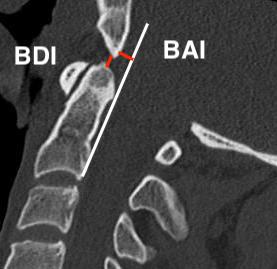

Basion-Dens Interval / BDI

- basion to tip of dens

- vertical displacement > 12 mm

Basion-Axial Interval / BAI

- basion to posterior border ondontoid

- anterior displacement > 4 mm